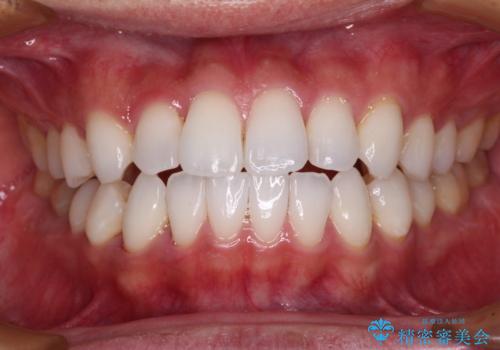

前歯のクロスバイトを改善 インビザラインによる矯正治療

今回は、ワイヤー装置を併用することなく治療を行い、トラブルなく、満足のいく歯列に整えることができました。

矯正治療の途中でホームホワイトニングを併用され、術前とは見違えるほどきれいな口元となりました。